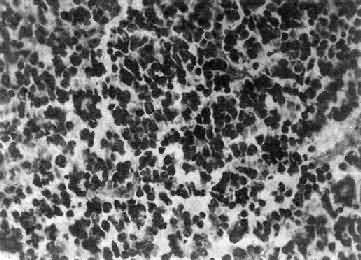

图16-25 室管膜瘤 瘤细胞为圆形或卵圆形,核染色质丰富,胞浆少,可见有细长的胞浆突起与血管相连,呈放射关,形成假菊形团 (二)髓母细胞瘤 髓母细胞瘤(medulloblastoma)好发于儿童,仅次于星形胶质细胞瘤而占第2位,其发生率占儿童颅内肿瘤的25%,发病年龄75%为15岁以下,偶见于成人,男性较女性为多(2~3:1)。 本瘤来源于小脑蚓部的原始神经上皮细胞或小脑皮质的胚胎性外颗粒层细胞,故本瘤主要见于小脑,在儿童多发生于小脑蚓部,在成人则多见于小脑半球。 肉眼观,瘤组织呈鱼肉状,色灰红。镜下,肿瘤由圆形、椭圆形或胡萝卜形细胞构成,胞核着色深,胞浆少而边界不清楚,有多少不等的核分裂像。细胞密集,间质中有纤细的纤维,血管不多。瘤细胞环绕一个嗜银性纤细的神经纤维中心作放射状排列形成典型的菊形团(图16-26),这对髓母细胞瘤的病理诊断有一定的意义。瘤细胞具有向神经元及神经胶质双向分化的潜能,既能向神经母细胞、节神经细胞分化,也能向胶质母细胞、星形胶质细胞分化。如瘤细胞侵入软脑膜,可在蛛网膜下腔脑脊液中广泛播散转移。